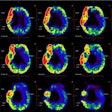

Will lecanemab approval increase PET scan volumes?